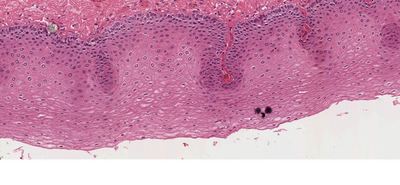

Question 2

Question

escoje la opcion correcta

Image:

95b927f8-29ae-48bc-a9ae-c75a53990f00.JPG (image/JPG)

Answer

epitelio plano estratificado no queratinzaddo

epitelio plano estratificado queratinizado

epitelio pseudoestratificado cilindrico ciliado con celulas caliciformes

urotelio

epitelio plano simple